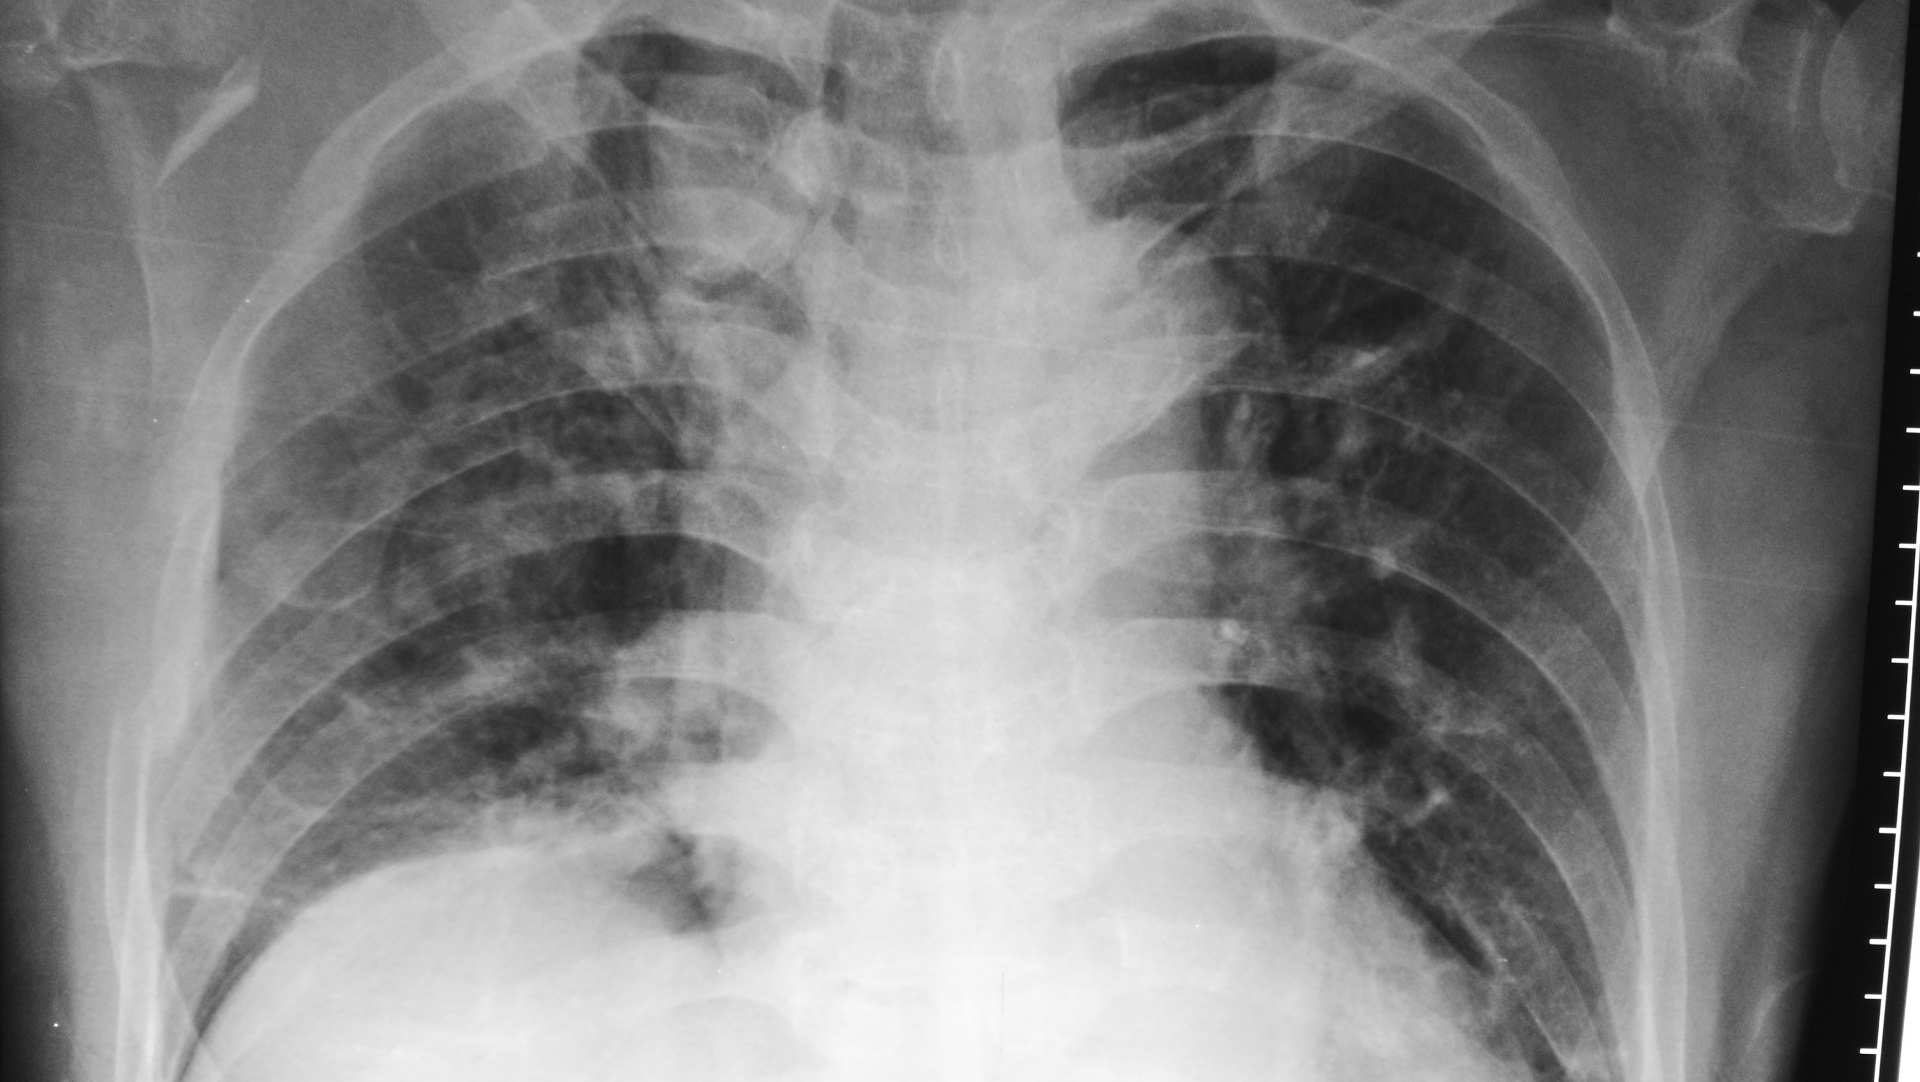

Prof Niall Ferguson (Toronto) presents the EOLIA trial, investigating extracorporeal membrane oxygenation (ECMO) in severe acute respiratory distress syndrome